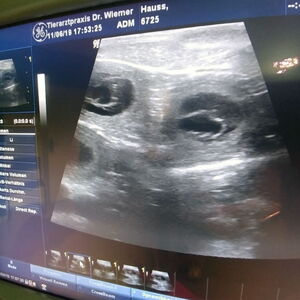

Am 10.08.2019 belegte Barolo die Hündin Avalon vom Felsengarten (Rufname Kimba).

Die beiden waren sich sofort sympathisch, aber erst als die „große Schwester“, die in Begleitung dabei war, im Camper verblieb, hat sich Barolo getraut.

So hat Kimba vom 10. auf den 11.10.2019 ihren A-Wurf mit 11 Welpen (7 R | 4 H) zur Welt gebracht.